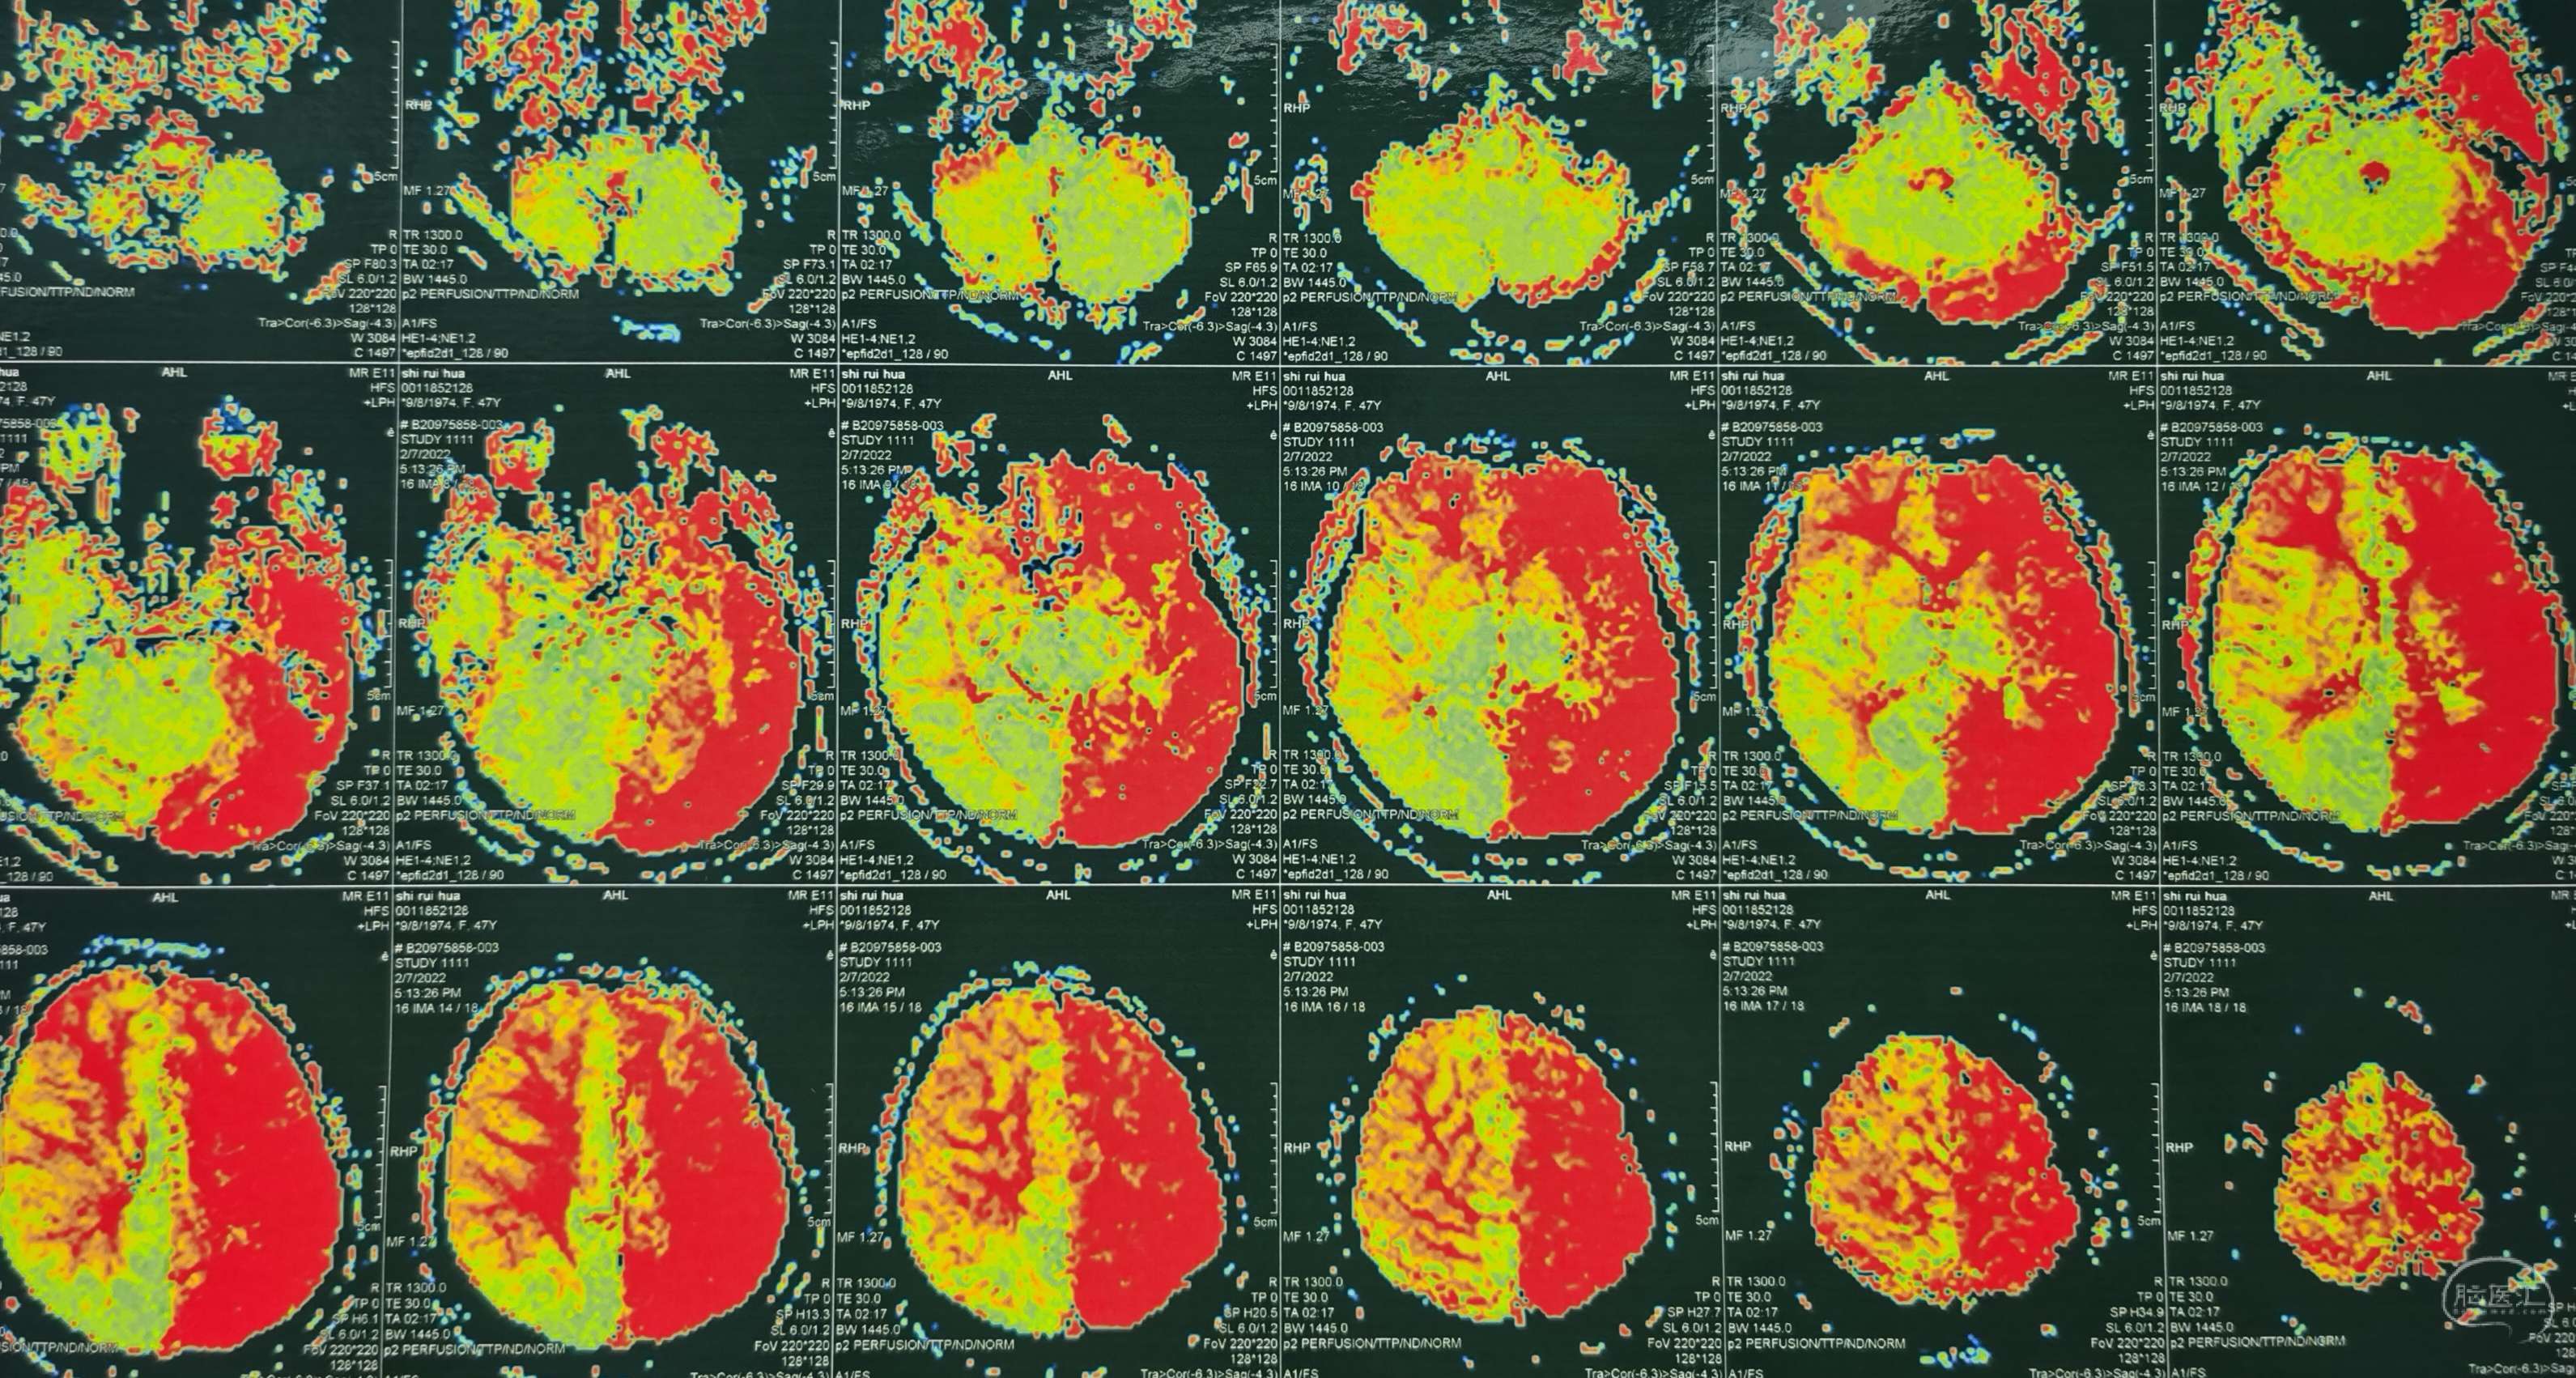

脑灌注提示:左侧大脑半球低灌注缺血。

脑灌注提示:右侧大脑半球低灌注缺血。

脑灌注提示:双侧大脑半球低灌注缺血。

脑灌注提示:双侧大脑半球低灌注缺血。

脑灌注提示:双侧大脑半球低灌注缺血。